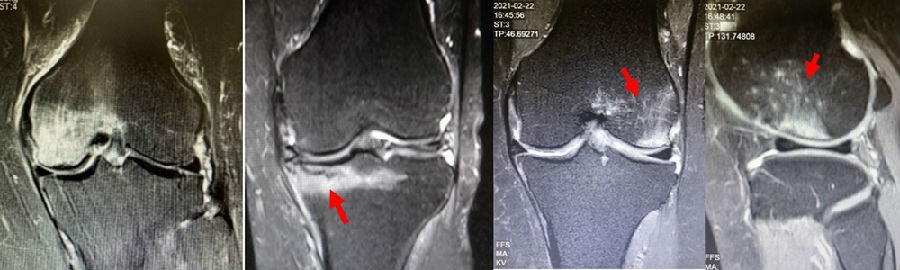

病例3:男,70岁,主诉右膝关节疼痛1年余。查体右膝无肿胀畸形,膝活动度0-120°,内侧间隙压痛。

已经累及44%的股骨内侧髁病变,半月板轻度突出,内侧后角水平撕裂

MRI上深度>20mm

保守治疗4个月后复查

保守治疗后效果欠佳,坏死范围扩大、塌陷

内侧半月板突出未见明显进展